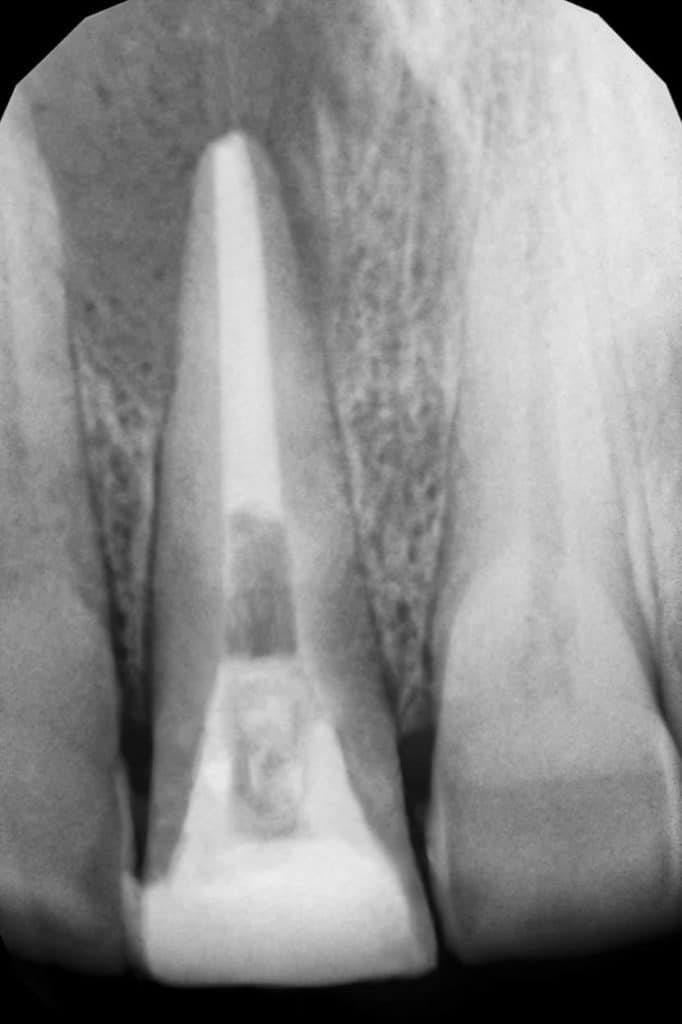

This is a case of discolored right central incisor for a 21 years-old-male patient. He had a history of previous trauma 2 years ago to his tooth and fracture, that was managed with a composite restoration. After clinical examination and x-ray imaging, the tooth was non-vital with periapical lesion.

After discussing the treatment options with the patient, he chose the direct composite veneer. The treatment included endodontic treatment, internal bleaching, direct composite veneer for the right central, and aesthetic reshaping for the laterals and left incisor also by composite restoration. The case completed in 2 sessions.